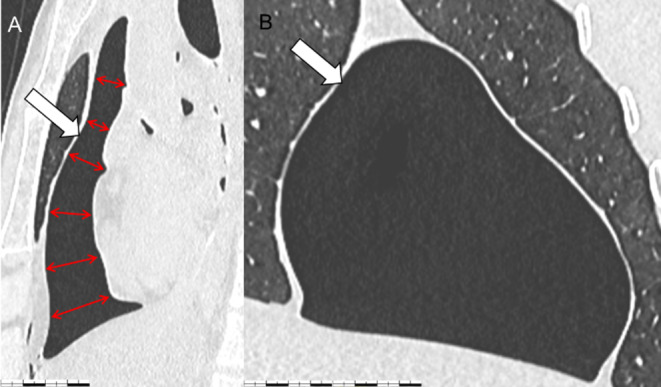

心包气肿(PPC)是指心包腔内存在气体,常导致心包填塞,死亡率高。本报告描述了一起案件,涉及一名33岁男子被发现死在离刀几米远的地方,他的衣服完好无损,没有进行任何复苏尝试。一条打了个结的围巾紧紧地围在他的脖子上,没有被勒死的痕迹。死后CT显示心包腔内气体271 ml,心脏扁平。法医检查发现两处胸部刺伤,一处刺穿心包,但没有刺穿心室,而另一处则是浅表刺伤。在没有复苏或放血的情况下,以及在窒息的情况下观察到的一些非特异性体征,支持压缩性PPC死亡的假设。这是法国第一例PPC病例报告,强调了这种实体在法医环境中的罕见性,并与文献中描述的其他未呈现相同特征的病例进行比较,指出了它所呈现的诊断困难和尸检CT在诊断中的重要性。

Pneumopericardium (PPC) is defined by the presence of gas in the pericardial cavity, often leading to cardiac tamponade and a high mortality rate. This report describes a case involving a 33-year-old man found deceased a few meters from a knife, his clothes intact, with no resuscitation attempt made. A knotted scarf was tightly fastened around his neck, without ligature mark. Post-mortem CT revealed 271 ml of gas in the pericardial cavity, with "flattened heart". The forensic examination revealed two thoracic stab wounds, one penetrated the pericardium without penetrating the heart chamber, while the second remained superficial. In the absence of resuscitation or exsanguination, and in the presence of some non-specific signs observed in the context of asphyxia, the hypothesis of death by compressive PPC was supported. This first French case report of PPC highlights the rarity of this entity in forensic settings, and comparison with other cases described in the literature which did not present the same characteristics points out the diagnostic difficulties it presents and the importance of post-mortem CT in diagnosis.